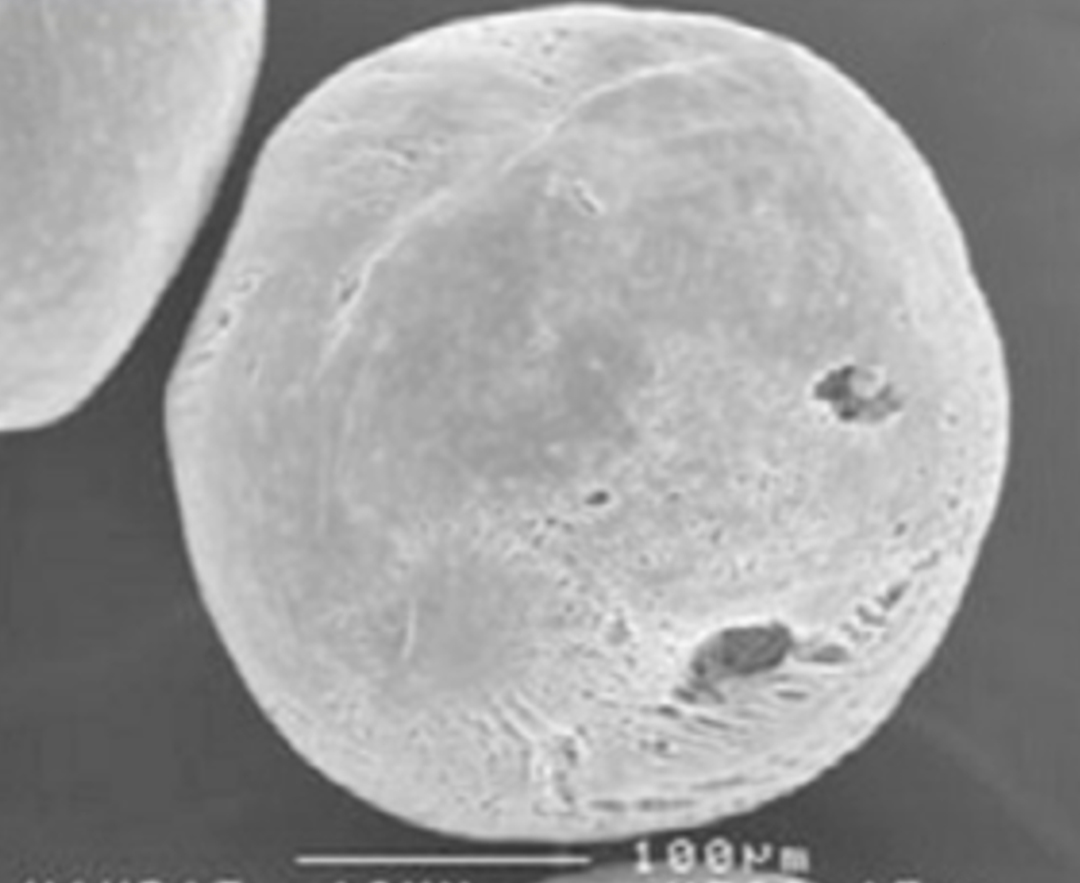

쥬베룩 볼륨 PDLLA 입자

쥬베룩 볼륨 PDLLA 입자는 매끄러운 구 형태의 입자를 가지고 있습니다.

이런 입자의 형태나 크기는 사람의 눈으로는 확인하기 어렵지만, 실제로 피부에 주입했을 때는 확연한 차이를 줄 수 있는데요.